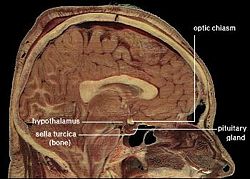

The hypothalamus, also known as the "master gland," is a supervising center in the brain that links the body's two control systems, the nervous system and the endocrine system, via interaction with the pituitary gland (hypophysis). The hypothalamus (from Greek áœ‘Ï€ÎżÎžÎ±Î»Î±ÎŒÎżÏ‚, "under the thalamus") is located below the thalamus, just above the brain stem, and occupies the major portion of the ventral region of the brain known as the diencephalon. The hypothalamus is found in all mammalian brains; in humans, it is roughly the size of an almond.

The hypothalamus gland regulates certain metabolic processes and other autonomic activities; it is a control center for functions of the autonomic nervous system. As needed, the hypothalamus synthesizes and secretes neurohormones, often called "releasing hormones," that control the secretion of hormones from the anterior pituitary gland.